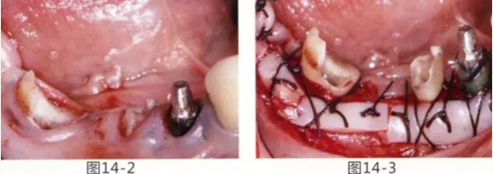

為了提高對修復體的術后效果,以生物學寬度,獲取附著齦為目的進行游離齦移植的病例。

圖14-1 修復體周圍角化牙齦較少,很難進行清潔的狀態(tài),并有緣下齲壞的發(fā)生。

圖14-2,3 徹底去除齲壞后,試圖通過游離齦移植獲取生物學寬度和附著齦。

圖14-7 配戴最終修復體完成5年后的狀態(tài)。保持良好。